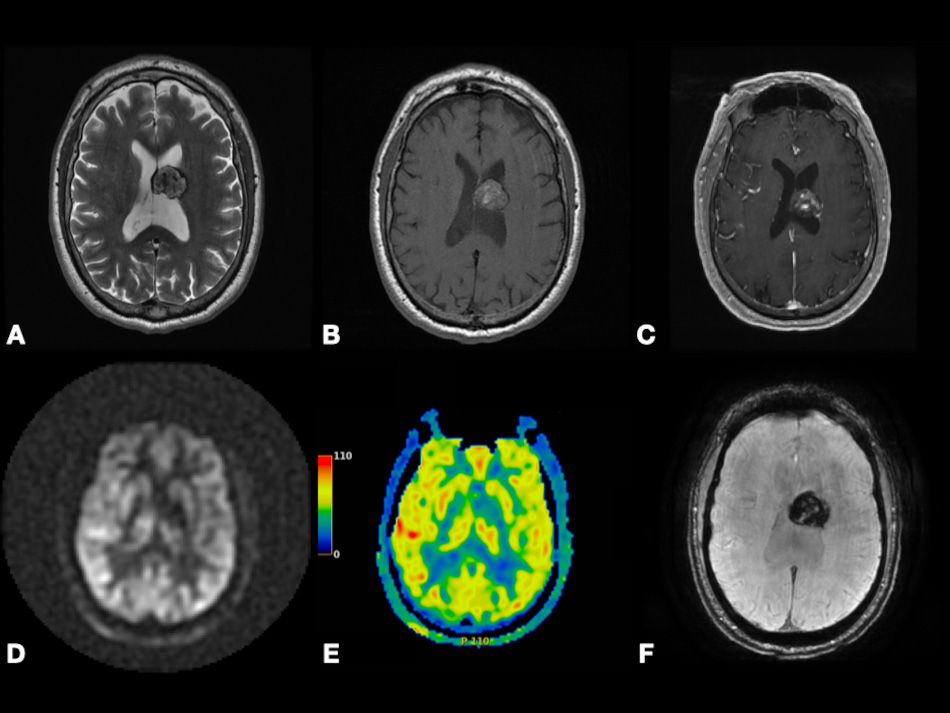

On DWI, Pavlisa et al. [94] found that ADCmean in SCs is significantly higher than both typical and atypical MGs. However, Ota et al. [74] found that there is no significant difference in ADC values between SCs versus MGs, PGs versus MGs, or SCs versus PGs. Thus, more clinical studies containing a large sample size are needed to evaluate the significance of DWI to differentiate between MGs and other extra-axial tumors. In Fig. 6, we present a case of right cerebral convexity atypical MG. The axial ADC map shows reduced diffusivity, while axial Pseudo-Continuous Arterial Spin Labeling (pcASL) source data and grayscale CBF map show marked heterogenous hyperperfusion. This demonstrates that MGs have high permeability and low diffusivity as mentioned in the literature. All of the previously mentioned studies differentiating between PG, SC, and MG using DCE, DSC, GRASP, and DWI are mentioned in Table 2 (Ref. [72, 73, 74, 76, 75, 88, 94]).

Fig. 6.Right cerebral convexity atypical meningioma (WHO Grade II). Axial ADC map (A), axial FLAIR (B), coronal fat-suppressed post-contrast T1-weighted (C), and axial SWI (F) images depicting large avidly enhancing plaque-like non-calcified mass with dural tail, reduced diffusivity, extensive vasogenic edema and mass effect with uncal herniation and ventricular trapping. Axial pcASL source data (D) and grayscale CBF map (E) depicting marked heterogenous hyperperfusion (red arrows). Abbreviations: ADC, Apparent diffusion coefficient; FLAIR, Fluid attenuated inversion recovery; SWI, Susceptibility weighted imaging; pcASL, Pseudo-Continuous Arterial Spin Labeling; CBF, cerebral blood flow.